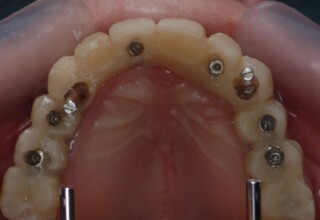

Lower jaw: extractions, direct implant placement and immediate loading (same day) with a transitional bridge.

Upper jaw: Sequential extractions, sequential implant placement and gradual incorporation in the temporary bridge so that the patient was never left without fixed teeth. The aim of the above approach was to have the patient in continuous functional and aesthetic reconstruction, without immediate loading due to anatomical restrictions. Old smiling photos of the patient were used because the natural shape of the teeth was completely lost due to repetitive prosthetic attempts. Tooth relationship and teeth-lip support was transferred to the temporary restorations. Two different transitional bridges were needed to fully estimate phonetics, mastication and esthetics. After the necessary adjustments were finalized, the temporary bridge was used as a guide for the permanent bridges.